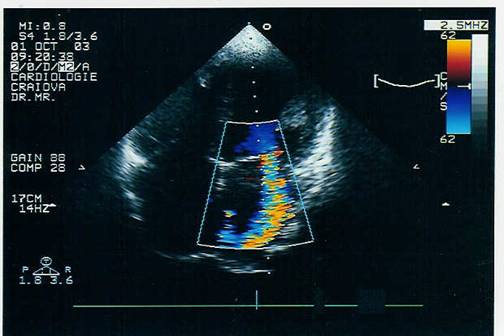

ECO color si Doppler pulsat permite cuantificarea regurgitarii evidentiind velocitatea maxima in sistola in atriul stang si se poate aprecia lungimea si aria jetului regurgitat pentru aprecierea gradului regurgitarii.